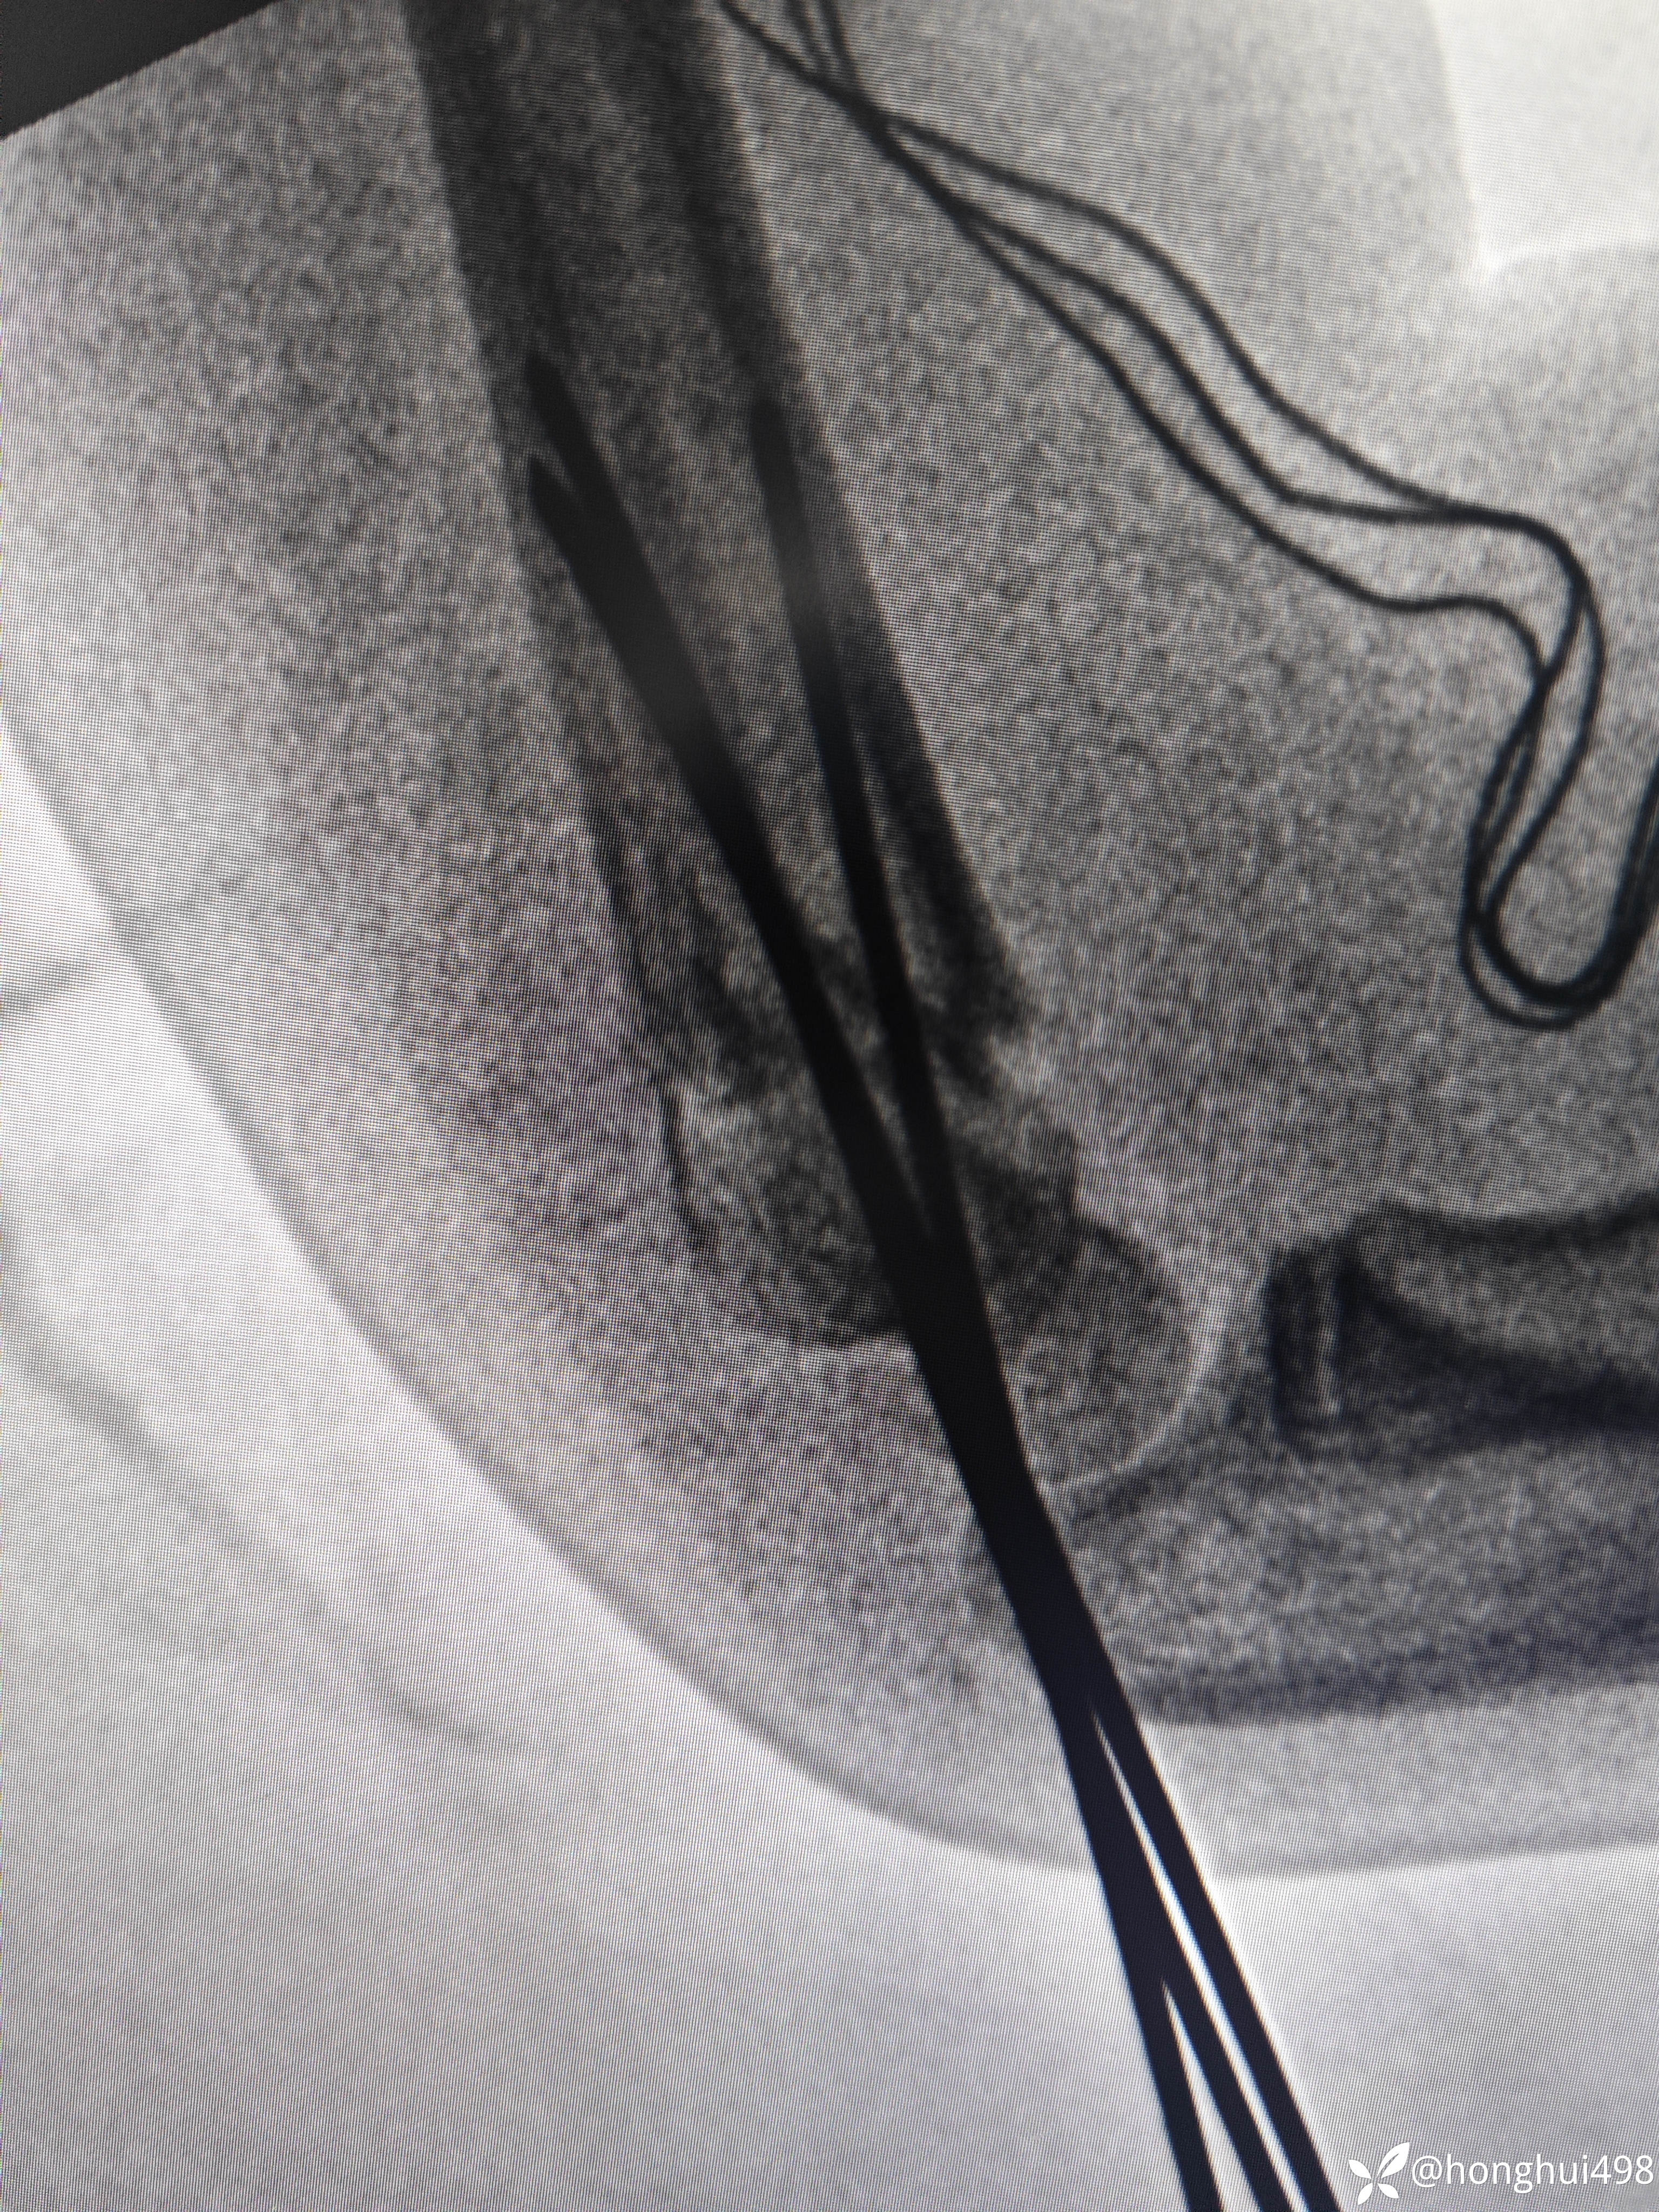

患儿女性,6岁,昨晚8点在家玩耍摔倒受伤,右肱骨髁上骨折。伤后在当地予手法复位草药外敷,伤后15小时来我院就诊,住院麻醉下闭合复位克氏针内固定。